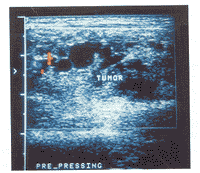

图5 血管畸形彩色多普勒超声图像,见块内虽有较多迂曲扩张的管道,但血流信号稀少,血管密度为2条/cm2

所有血管畸形在高频灰阶超声图像上亦表现为一团块状结构。但17处(85.0%)病变内为迂曲扩张的管道或管道与软组织相间的回声(图4),仅3处(15.0%)表现为单纯的实质性团块,10处(50.0%)伴有钙化。多普勒超声显示病变内血流信号稀少,血管密度为0~4条/cm2[(2.3±1.0)条/cm2],PSV仅为4.7~78.0 cm/s[(27.4±15.0)cm/s],RI为0.5~1.0(0.7±0.1)(图5,6)。